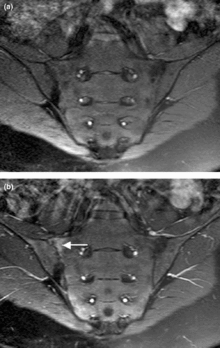

Magnetic resonance images of sacroiliac joints. Shown are T1-weighted semi-coronal magnetic resonance images through the sacroiliac joints (a) before and (b) after intravenous contrast injection. Enhancement is seen at the right sacroiliac joint (arrow, left side of image), indicating active sacroiliitis. This patient had psoriatic arthritis.